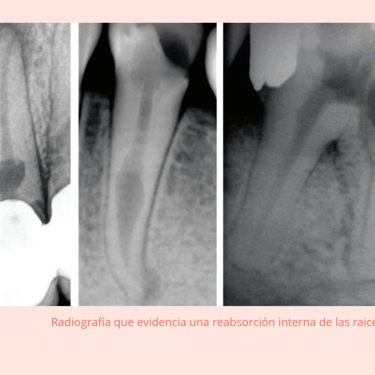

Radiografías: Se toman radiografías para visualizar el grado de reabsorción en la raíz del diente. En algunos casos, puede ser necesaria una tomografía computarizada (CBCT) para obtener imágenes más detalladas.

Resultados esperados: Si la reabsorción es leve, el diente puede ser tratado con endodoncia. Si es extensa, puede ser necesario extraer el diente.